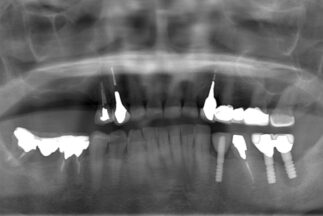

- Before

【症例ステータス】

| 年齢 | 性別 | 治療期間 | 治療費概算 |

|---|---|---|---|

| 57歳 | 女性 | 2年 |

480万 ※費用は範囲によって異なります。 |

| 主訴 | |

|---|---|

| 治療内容 | 上顎右側サイナスリフト インプラント埋入上顎3本 下顎3本 上部構造モノリシックジルコニアクラウン修復 |

| リスクについて | インプラント周囲炎 スクリューの緩みなど |